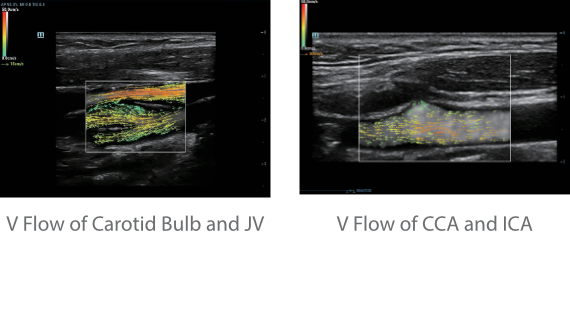

Neben der erstklassigen Bildqualit?t verbessert Resona 7 auch die klinischen Forschungsm?glichkeiten mit dem revolution?ren V Flow f├╝r die vaskul?re h?modynamische Bewertung und der intelligentesten Ebenenerfassung aus 3D-Datens?tzen f├╝r die f?tale ZNS-Diagnose. Mit der Kombination aus intuitiver, gestenbasierter Multi-Touch-Bedienung und allen wichtigen klinischen Funktionen ist das Resona 7 ein echter Wegbereiter f├╝r neue Ultraschall-Innovationen.

Die St?rken des Resona 7 sind bis ins kleinste Detail durchdacht. Seine erstklassige Bildqualit?t ist das Ergebnis einer erfolgreichen Fusion. Mindray und Zonare Medical Systems haben ihren Kernkompetenzen geb├╝ndelt, um ein Premiumsystem Wirklichkeit werden zu lassen. Dank der Vector Flow-Funktion k?nnen bei Gef??untersuchungen mehr als 400 Bilder pro Sekunde dargestellt werden. Somit entstehen ganz neue M?glichkeiten der Diagnose.